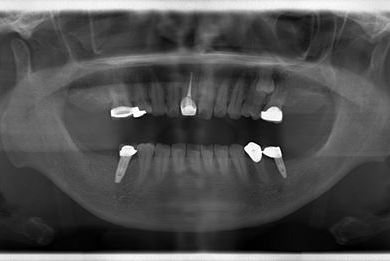

インプラントの症例写真 IMPLANT

インプラント治療+セラミック治療

| 性別/年齢 | 女性 / 47歳 | ||||||||||||||||||||||||||||||||

| 主訴 | 前歯や、下の奥など、何本か気になる歯がある。 | ||||||||||||||||||||||||||||||||

| 治療方針 | インプラント治療により、機能的・審美的回復を行う。 | ||||||||||||||||||||||||||||||||

| 治療内容 | インプラント2本、メタルボンドセラミッククラウン4本、ジルコニアフレームオールセラミッククラウン1本(オールセラミック用土台1本) | ||||||||||||||||||||||||||||||||

| 総治療費 | 1,188,864円 | ||||||||||||||||||||||||||||||||

| 治療期間 | 2年10ヶ月 |